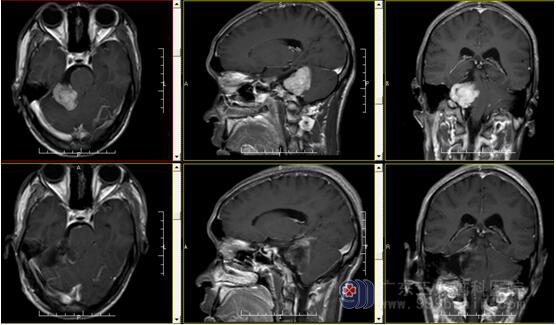

术前MR报告示右侧桥小脑角区示一团块状长T1稍长T2信号影,FLAIR序列呈等信号,大小约47mm×32mm×35mm;增强后呈明显强化,邻近右侧听神经增粗、强化;邻近右侧小脑半球示斑片状长T1长T2信号影,FLAIR序列呈高信号。